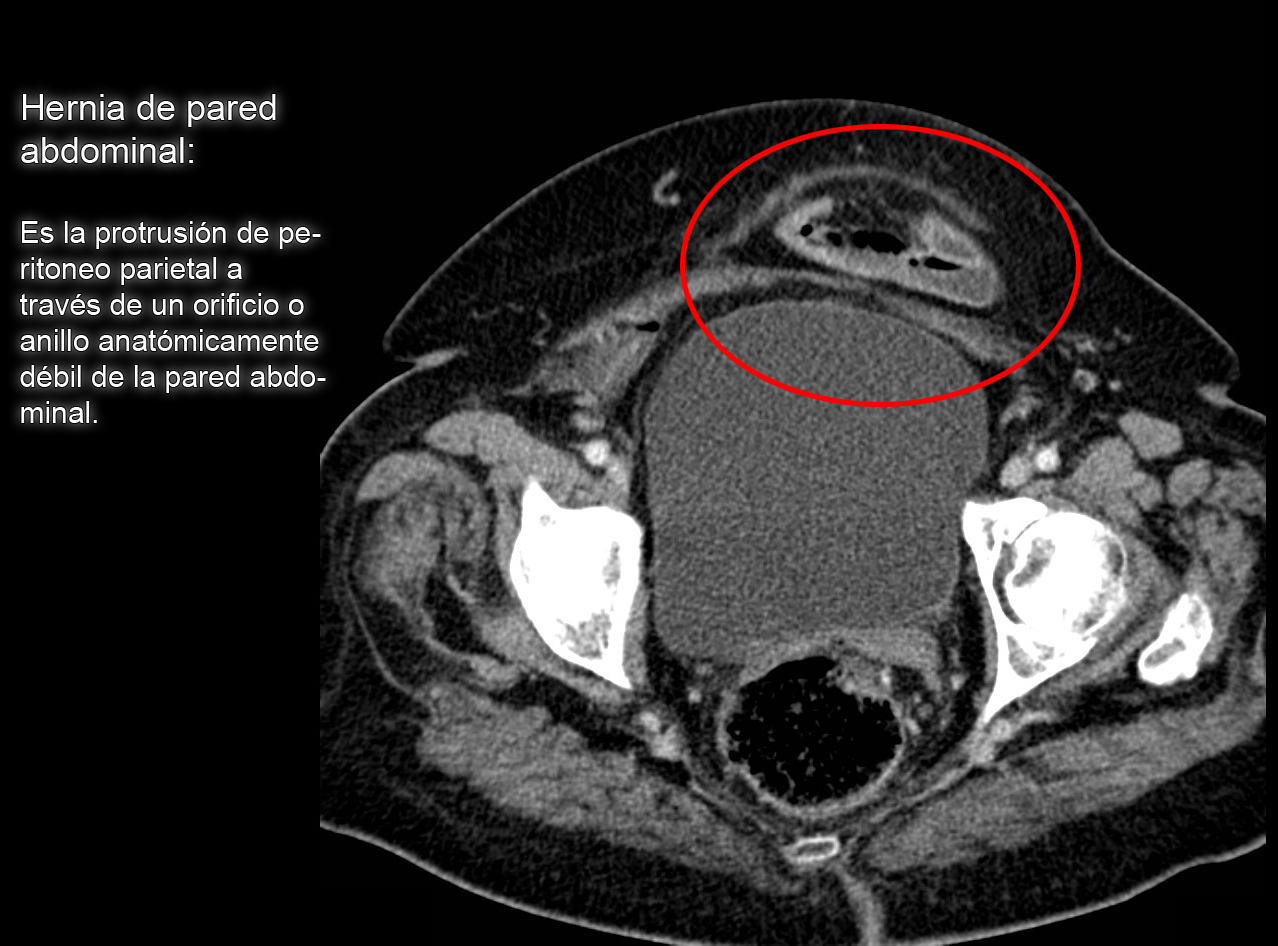

Tomografía Axial Computarizada (TAC) del abdomen que muestra una

Tomografía Computada para estudiantes. Hernia de pared abdominal.